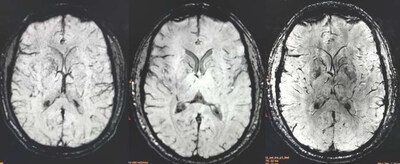

ATLANTA, April 7, 2026 /PRNewswire/ -- Alzamend Neuro, Inc. (Nasdaq: ALZN) ("Alzamend"), a clinical-stage biopharmaceutical company focused on developing novel products for the treatment of Alzheimer's disease ("Alzheimer's"), bipolar disorder type 1 ("BD"), major depressive disorder ("MDD") and post-traumatic stress disorder ("PTSD"), today announced encouraging pharmacodynamic findings from a brain magnetic resonance spectroscopy ("MRS") analysis conducted in healthy human subjects (N=6) in a trial conducted at Massachusetts General Hospital. The study assessed changes in five key brain metabolites across 18 brain regions when participants received two-weeks of blood bioequivalent and lithium-dose equivalent AL001 or lithium carbonate relative to baseline. Early data suggest AL001 may work like lithium carbonate by selectively impacting brain chemicals where needed, however, AL001 appears to be leaving other, healthy brain chemicals more undisturbed than lithium carbonate, a potentially meaningful tolerability advantage. These interpretations are based solely on qualitative review of all analyses and need to be further statistically confirmed in additional patient populations, the first of which is currently underway.

Brain metabolite concentrations were assessed using ultra-high field high-resolution magnetic resonance spectroscopic imaging (MRSI) in six healthy volunteers following blood-bioequivalent and lithium-dose equivalent 14-day multiple doses of AL001 and lithium carbonate treatments in a randomized, crossover design across 18 brain regions. The five metabolites analyzed were: total creatine (Cr+PCr), glutamate (Glu), glycerophosphocholine plus phosphocholine (GPC+PCh), myo-inositol (Ins), and N-acetylaspartate plus N-acetylaspartylglutamate (NAA+NAAG). Statistical analyses used the Wilcoxon signed-rank test and Hedges' g effect-size measure, with a pre-specified ≥20% absolute threshold to screen for pharmacodynamically relevant signals. The MRS neuroimaging methodology was developed by the lab of Dr. Ovidiu C. Andronesi, the study's principal investigator, Associate Professor of Radiology at Harvard University, and the Director of Multinuclear MR Imaging, Martinos Center for Biomedical Imaging, Department of Radiology, Massachusetts General Hospital, Harvard Medical School. All findings are exploratory, hypothesis-generating, and require confirmation in adequately powered studies.